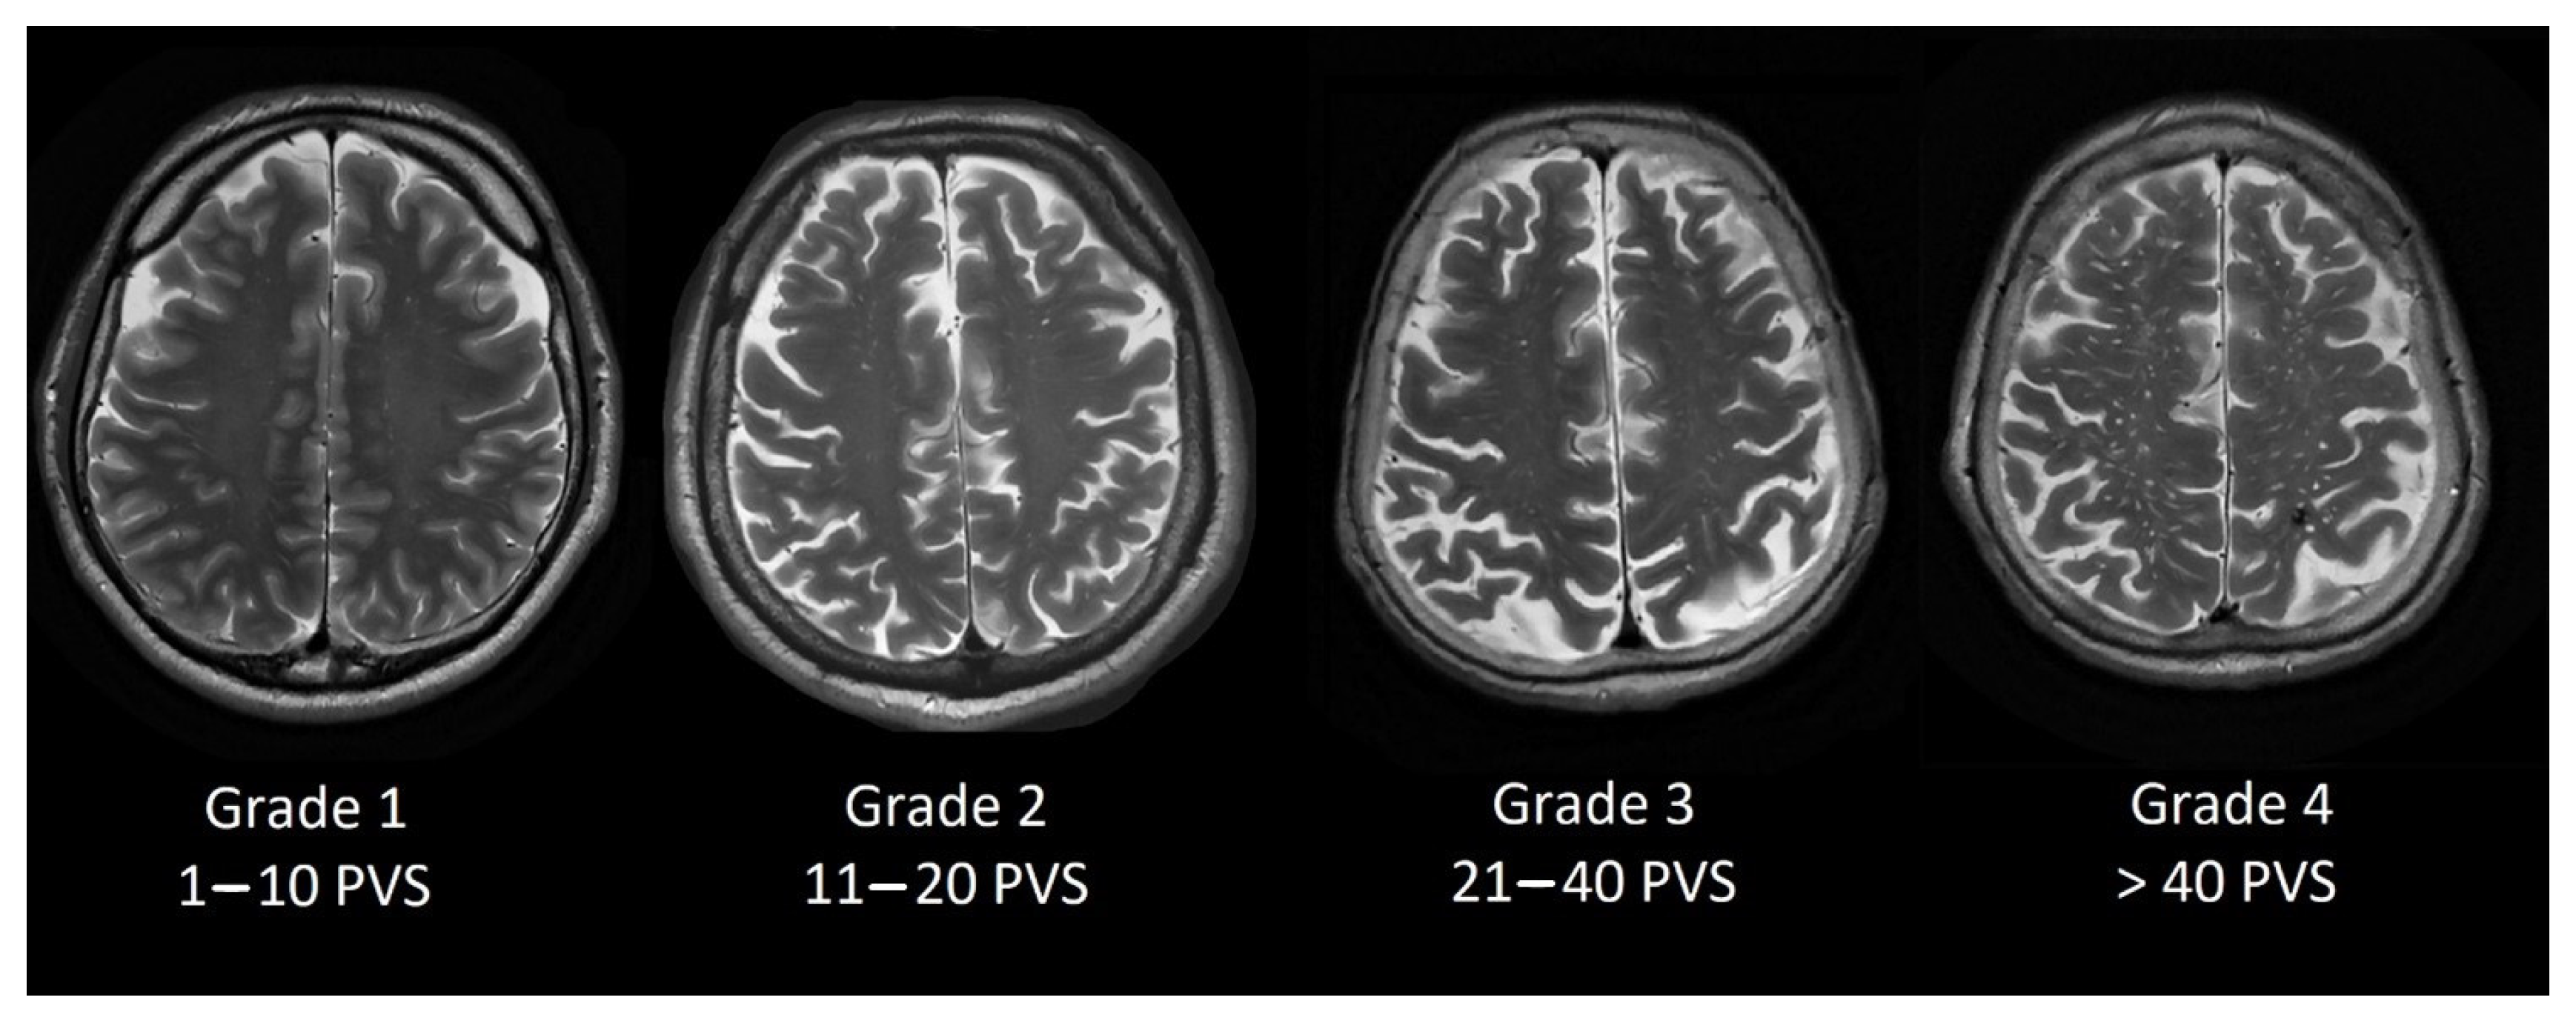

Perivascular space grading was partially based on Potter et al. [13] grading scale. We evaluated basal ganglia PVS (Type 1, see Figure 1) and centrum semiovale PVS (Type 2, see Figure 2) by the rating scale: grade 0–no PVS dilatation; Grade 1–1 to 10 dilatated PVS; Grade 2–11 to 20 dilatated PVS; Grade 3–21 to 40 dilatated PVS; Grade 4–>40 dilatated PVS.

Figure 2. Dilated PVS in centrum semiovale from Grade 1 to Grade 4.